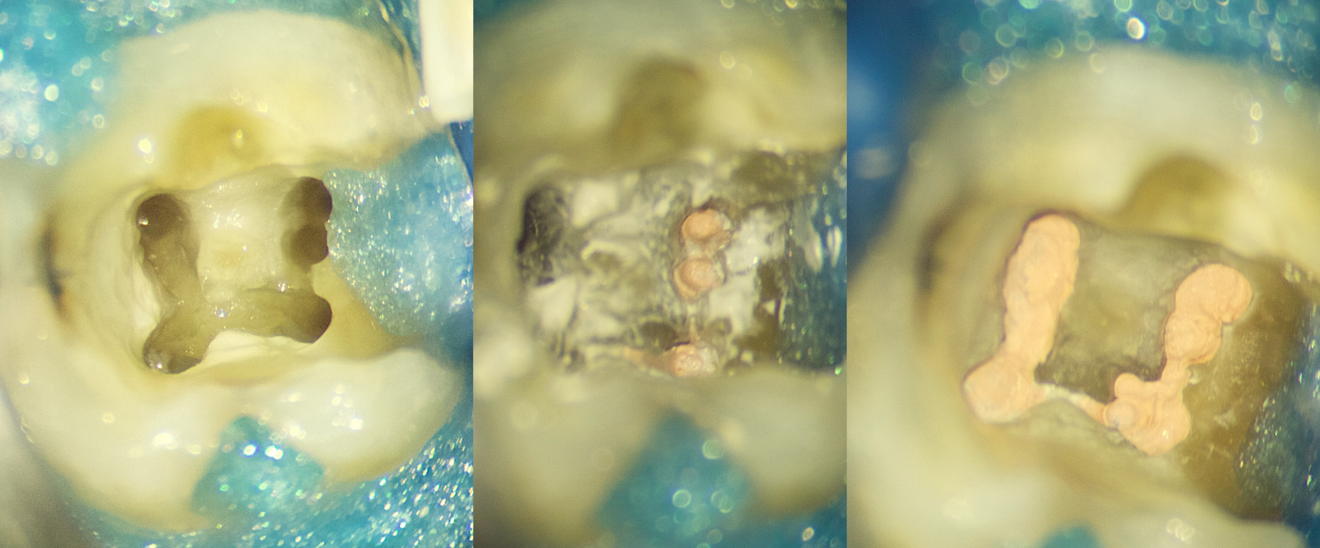

Case 2 (Figs. 8 & 9)

A patient with a mandibular third molar diagnosed with irreversible pulpitis and symptomatic apical periodontitis was referred to my practice. Under high magnification, the canal entrances were negotiated using medium-power ultrasonic instruments and D-perfect C Files (Shenzhen Perfect Medical Instruments). Special care was given to the coronal portion of the root canal, especially to the mesiobuccal canal, owing to the scouted double curvatures. Pressureless mechanical pre-flaring was done to reduce the coronal interferences (cervical dentinal triangle—red triangle), which can place huge stress on the shaping files, leading to procedural errors such as instrument separation and transportation, thereby increasing the difficulty of an initially straightforward case.

Mechanical pre-flaring in such a case can be done using either the starter file (20/0.10) or the apical 3–4 mm of the 25/0.06 shaping file or even both. The mode of action of these files is brushing motion towards the outer walls.

Fig. 8

Fig. 9